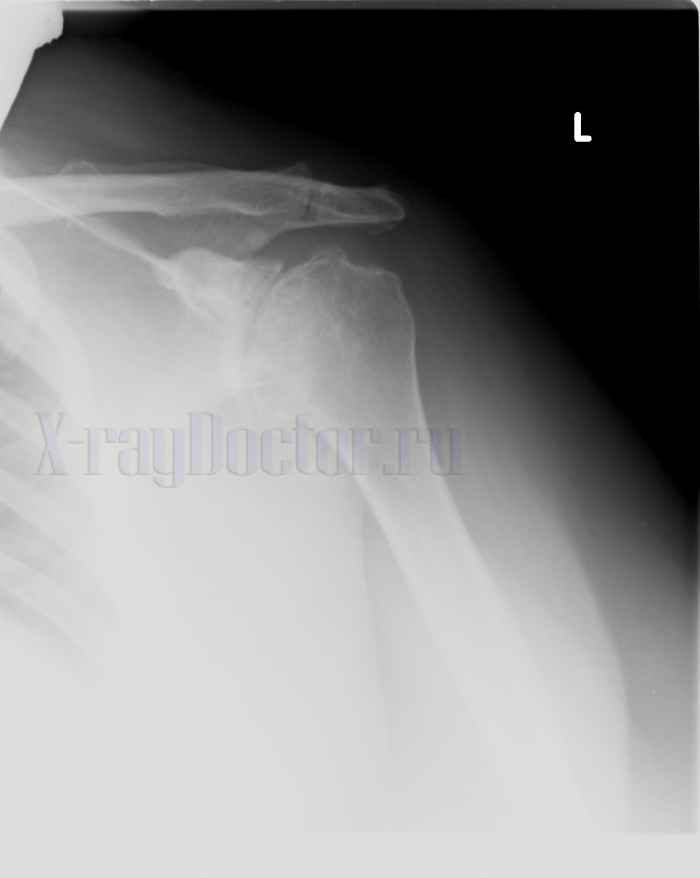

Рентгеновский снимок при артрозе плечевого сустава

Протокол описания: На представленной рентгенограмме левого плечевого сустава визуализируется деформация суставной поверхности плечевой кости